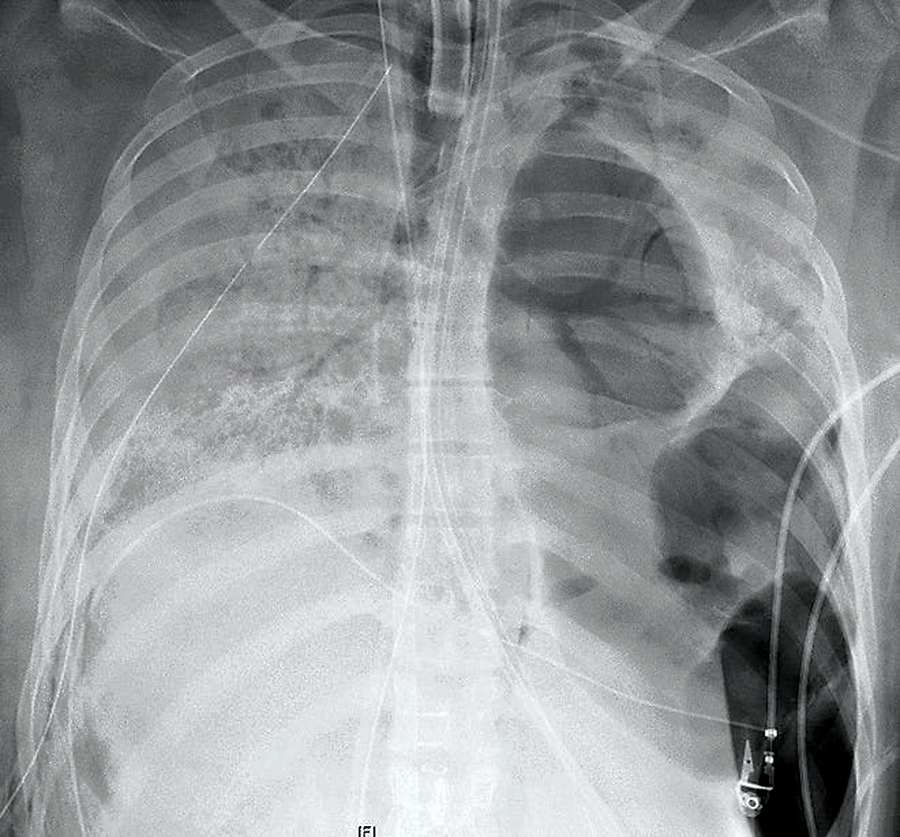

엑스레이에 나타난 폐에 구멍이 난 모습.

12일 USA 투데이는 코로나19 바이러스 감염으로 양쪽 폐에 다수의 구멍이 생기고 심장, 횡격막의 섬유화가 진행돼 치료가 불가능해 보였던 20대 여성이 시카코 노스웨스턴대 메모리얼병원에서 지난 주 10시간이 넘는 수술 끝에 양쪽 폐를 성공적으로 이식받았다고 보도했다.

코로나 19 중증환자에 대한 폐 이식수술은 미국에서 처음으로 성공한 것이어서 코로나19 중증 환자를 치료에 새로운 희망이 될 것으로 기대된다. 20대로 알려진 인 이 환자는 지난 금요일 노스웨스턴 메모리얼 병원에서 수술을 받기 전 거의 두 달 동안 인공호흡기 등을 단 채 생명을 유지하고 있었다. 이 수술을 한 앙키트 바라트 박사는 “코로나 19 바이러스가 폐에 다수 발생한 구멍들을 통해 흉벽에 달라 붙어 있는 상태여서 10시간 동안 진행된 수술은 매우 도전적이었다”고 말했다.